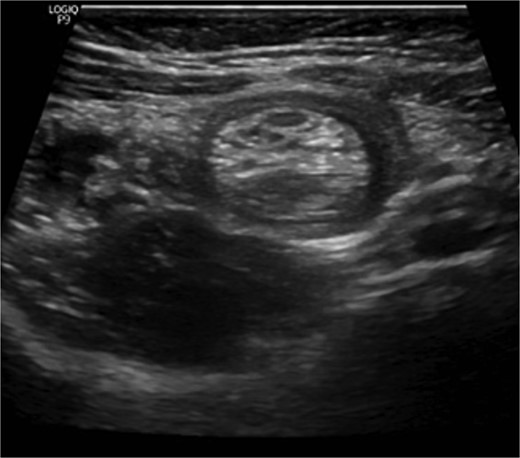

Histopathological assessment (Fig. 4) revealed small intestinal mucosa showing ectopic gastric tissue composed of foveolar and oxynetic glands, compatible with MD. In addition, a tumor was found. Composed of ribbons and cords of monomorphic cells with salt-pepper chromatin pattern and plenty of cytoplasm that show strong expression of Synaptophysin, INSMI, and Chromogranin A. Ki-67 proliferation index is low; <1% of tumor cells, compatible with NET grade 1. The tumor measured 4 mm, with no evidence of perineural or vascular invasion. Following the surgery, the child made a complete recovery and remained free of further episodes of intussusception during one year of follow-up in the clinic.

A: Low power magnification of H&E stain; tumor nest in the wall of the bowel, ribbons and cords of monomorphic cells with salt-pepper chromatin pattern, typically seen in endocrine tumors. B: Neuroendocrine tumor in the wall of bowel and fat (×20 magnification). C: Solid nest of tumor (high power magnification ×40). D: Immunohistochemistry Synaptophysin positive; Synaptophysin stains vesicles in neuroendocrine cells. E: Immunohistochemistry INSMI positive, a specific marker for neuroendocrine. F: Immunohistochemistry AE1/AE3 positive, a neuroendocrine marker.